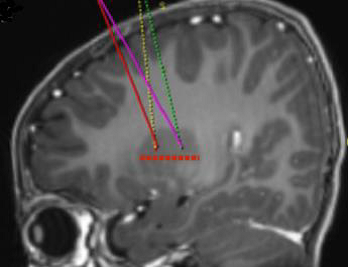

Die angestrebten Infusionsstellen werden gemäß der stereotaktischen neurochirurgischen Standardpraxis definiert. Upstaza wird als eine bilaterale Infusion (2 Infusionen pro Putamen) mit einer intrakraniellen Kanüle verabreicht. Die 4 endgültigen Ziele für jeden Zielkanal sind als 2 mm dorsal zu (über) den vorderen und hinteren Zielpunkten in der mittelhorizontalen Ebene zu definieren (Abbildung 1).

Abbildung 1 Die vier Zielpunkte für die Infusionsstellen